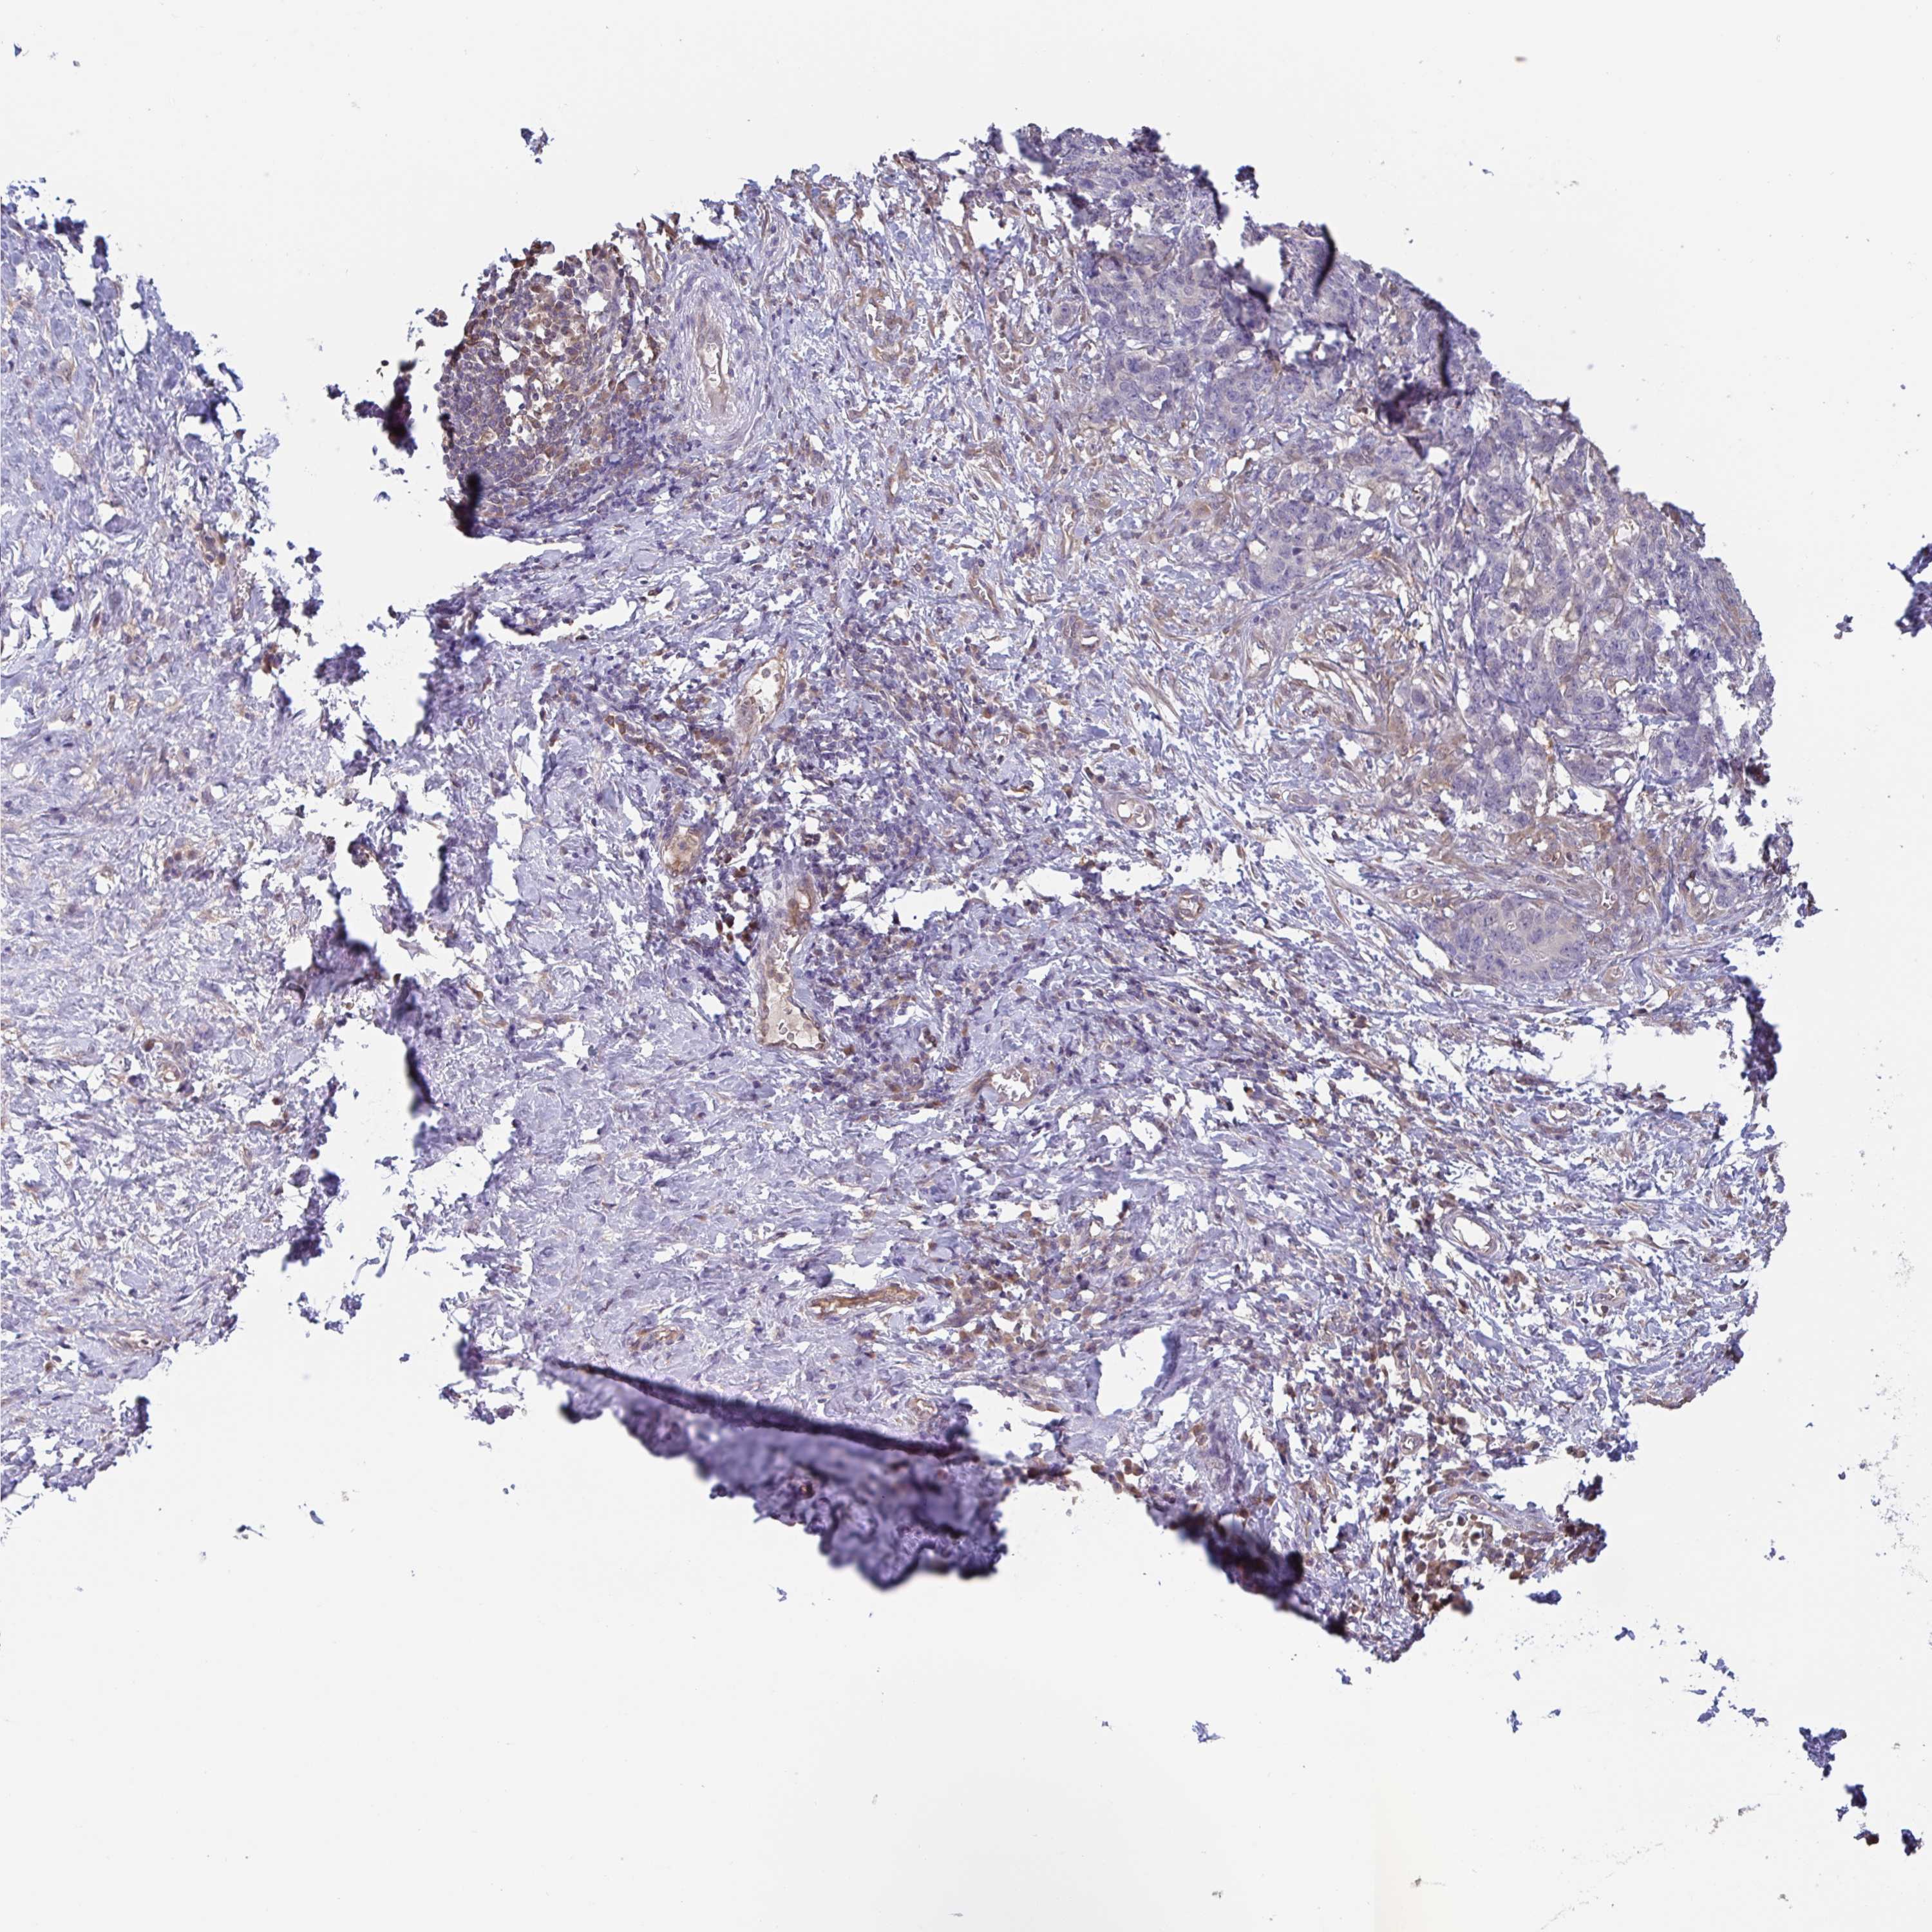

STOMACH CANCER - Protein expressioni

A mouse-over function shows sample information and annotation data. Click on an image to view it in a full screen mode. Samples can be filtered based on level of antibody staining by selecting one or several of the following categories: high, medium, low and not detected. The assay and annotation is described here.

Note that samples used for immunohistochemistry by the Human Protein Atlas do not correspond to samples in the TCGA dataset.

Antibody stainingi

Antibody staining in the annotated cell types in the current human tissue is reported as not detected, low, medium, or high, based on conventional immunohistochemistry profiling in selected tissues. This score is based on the combination of the staining intensity and fraction of stained cells.

Each image is clickable and will lead to virtual microscopy that enables deeper exploration of all samples and also displays staining intensity scores, fraction scores and subcellular localization as well as patient and tissue information for each sample.

Antibody HPA024524

Antibody HPA053090

Staining

High

Medium

Low

Not detected

Intensity

Strong

Moderate

Weak

Negative

Quantity

>75%

75%-25%

<25%

None

Location

Nuclear

Cytoplasmic/membranous

Cytoplasmic/membranous,nuclear

Adenocarcinoma, NOS